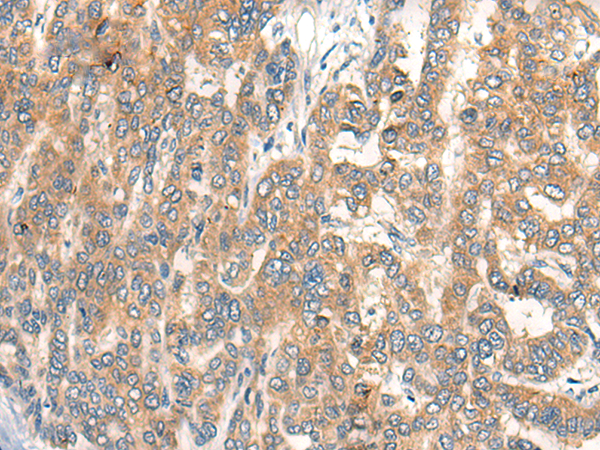

IHC positive control: |

Human liver cancer |

IHC Recommend dilution: |

25-100 |